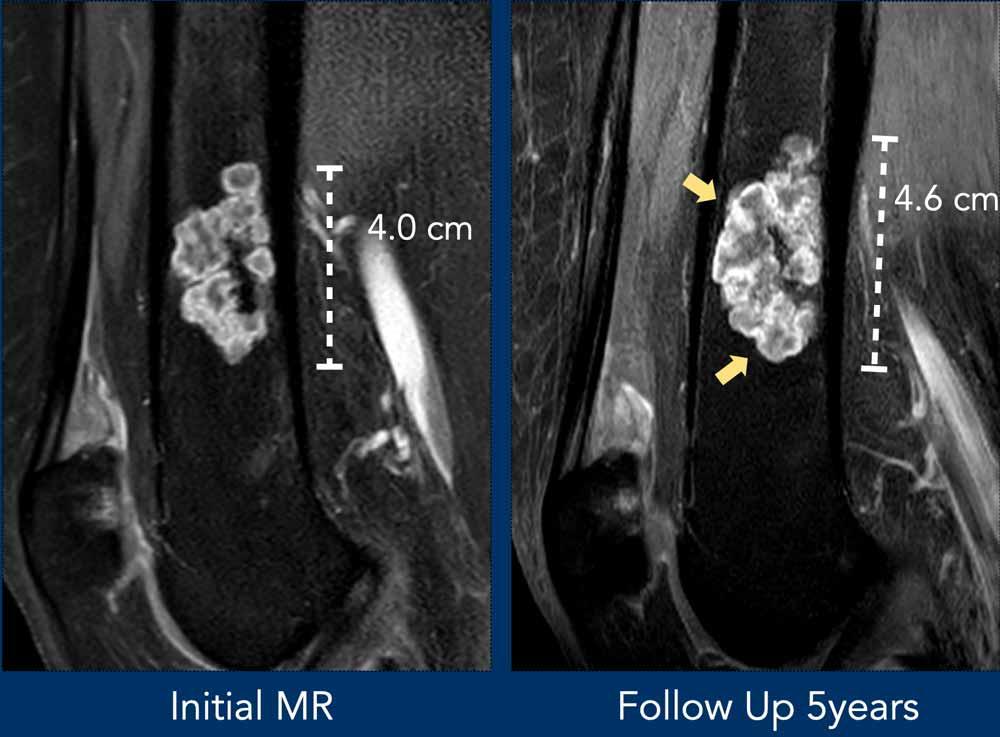

Trường hợp này đã được trình bày trước đây.

Nhìn lại hình ảnh MRI trước đó được thực hiện 5 năm trước, tổn thương đã tăng trưởng 6 mm theo chiều sọ-đuôi.

Cũng lưu ý sự mở rộng của tổn thương về phía trước (mũi tên vàng).

Không có hiện tượng mỏng vỏ xương, phù tủy xương hay viêm màng xương.

This lesion is an

ACT and remains in follow-up.